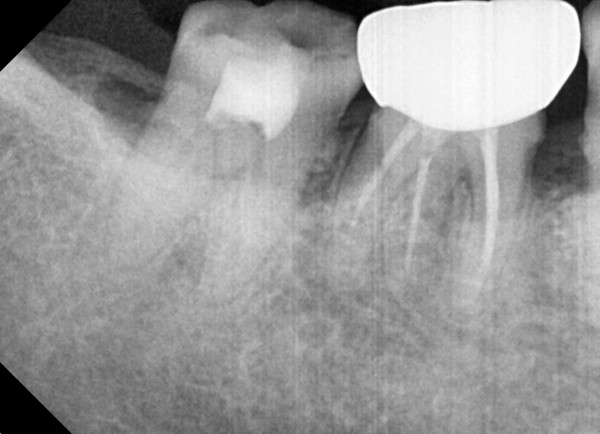

충치치료&신경치료 하루에 끝나는 신경치료

c36d6f431fa4d39e6efca10cb66686a2_1767329888_2192.jpg